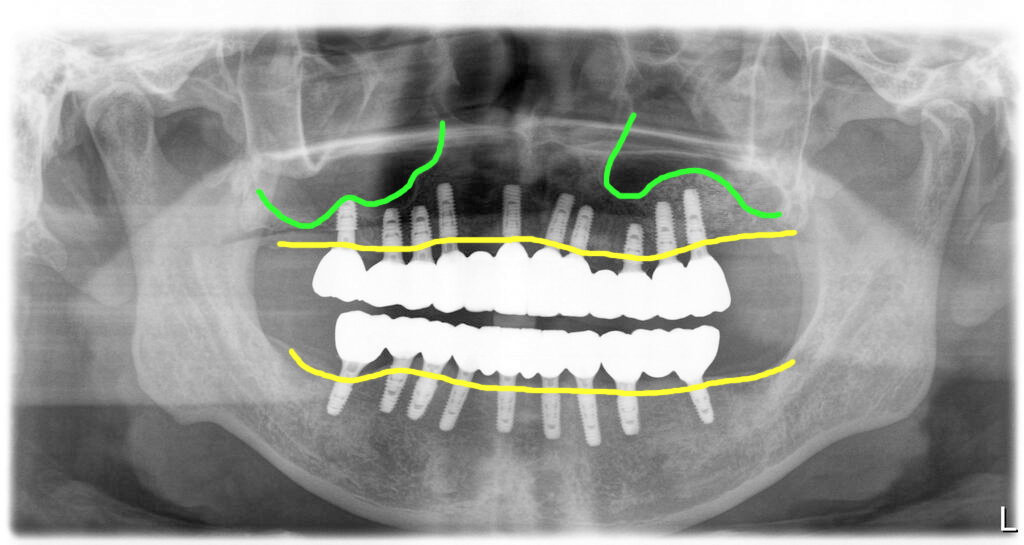

이제 파노라마 엑스레이로 구체적 설명을 해 드릴께요.

전체 치아를 모두 발치하고 임플란트를 식립했습니다. 우측 위쪽의 상악동부위에는 간단한 방식으로 거상술을 진행했습니다.(초록색)

그러나, 좌측 위 어금니 부위쪽 상악동은 이미 상악동이 뚫려 있어 우선 발치만 진행을 해 두었습니다.

그렇게 해서 모든 치아 발치, 염증제거, 위쪽에 8개, 아래 9개의 임플란트를 식립했습니다. 저는 임플란트를 넉넉하게 심는 편입니다. 그 이유는 아래에 링크를 걸어두겠습니다.

그리고 다시 2개월 후 상악동 윈도우수술을 해서 뼈이식을 한 모습의 파노라마 사진입니다. 핑크색부분이 윈도우 방식으로 뼈이식을 한 부위입니다.

상악동거상술 뼈이식을 한 후 6개월 기다렸다가 임플란트를 심고 다시 6개월을 기다렸다가 최종적인 보철을 완성한 모습입니다. 그렇게 해서 이 환자는 수술을 시작하고 약 1년 반 정도의 치료기간이 걸린 경우입니다. 보통 이렇게 긴 시간이 걸리는 경우는 드물지만 환자의 상태가 허락되지 않으면 이렇게 긴 시간이 필요하기도 합니다.